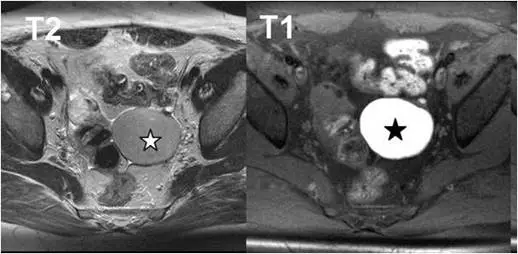

35歲女性病患,主訴下腹痛,磁振造影檢查發現骨盆腔有囊狀病灶(星號),在 T2 加權影像(左圖)呈稍低訊號, T1加權影像(右圖)呈高訊號。其診斷為何? 圖片描述

左圖為骨盆橫斷面T2加權影像,可見星號處囊狀病灶內部訊號介於肌肉及自由液體間,呈稍低於典型液體的中等至低訊號,符合「T2 shading」現象(chocolate cyst因反覆月經性出血,濃縮的鐵血黃素及蛋白質使其T2訊號降低) (pubmed.ncbi.nlm.nih.gov)。右圖為同部位T1加權影像,病灶全區高訊號,代表含有亞急性血液或高蛋白質含量的血腫成分 (radiologica.org)。整體影像符合典型子宮內膜異位囊腫的影像表現。

• 選項A 巧克力囊腫(chocolate cyst)

子宮內膜異位囊腫在MRI上最具代表性的是T1高訊號(血性內容物)及T2 shading sign(訊號暗影),與本例完全一